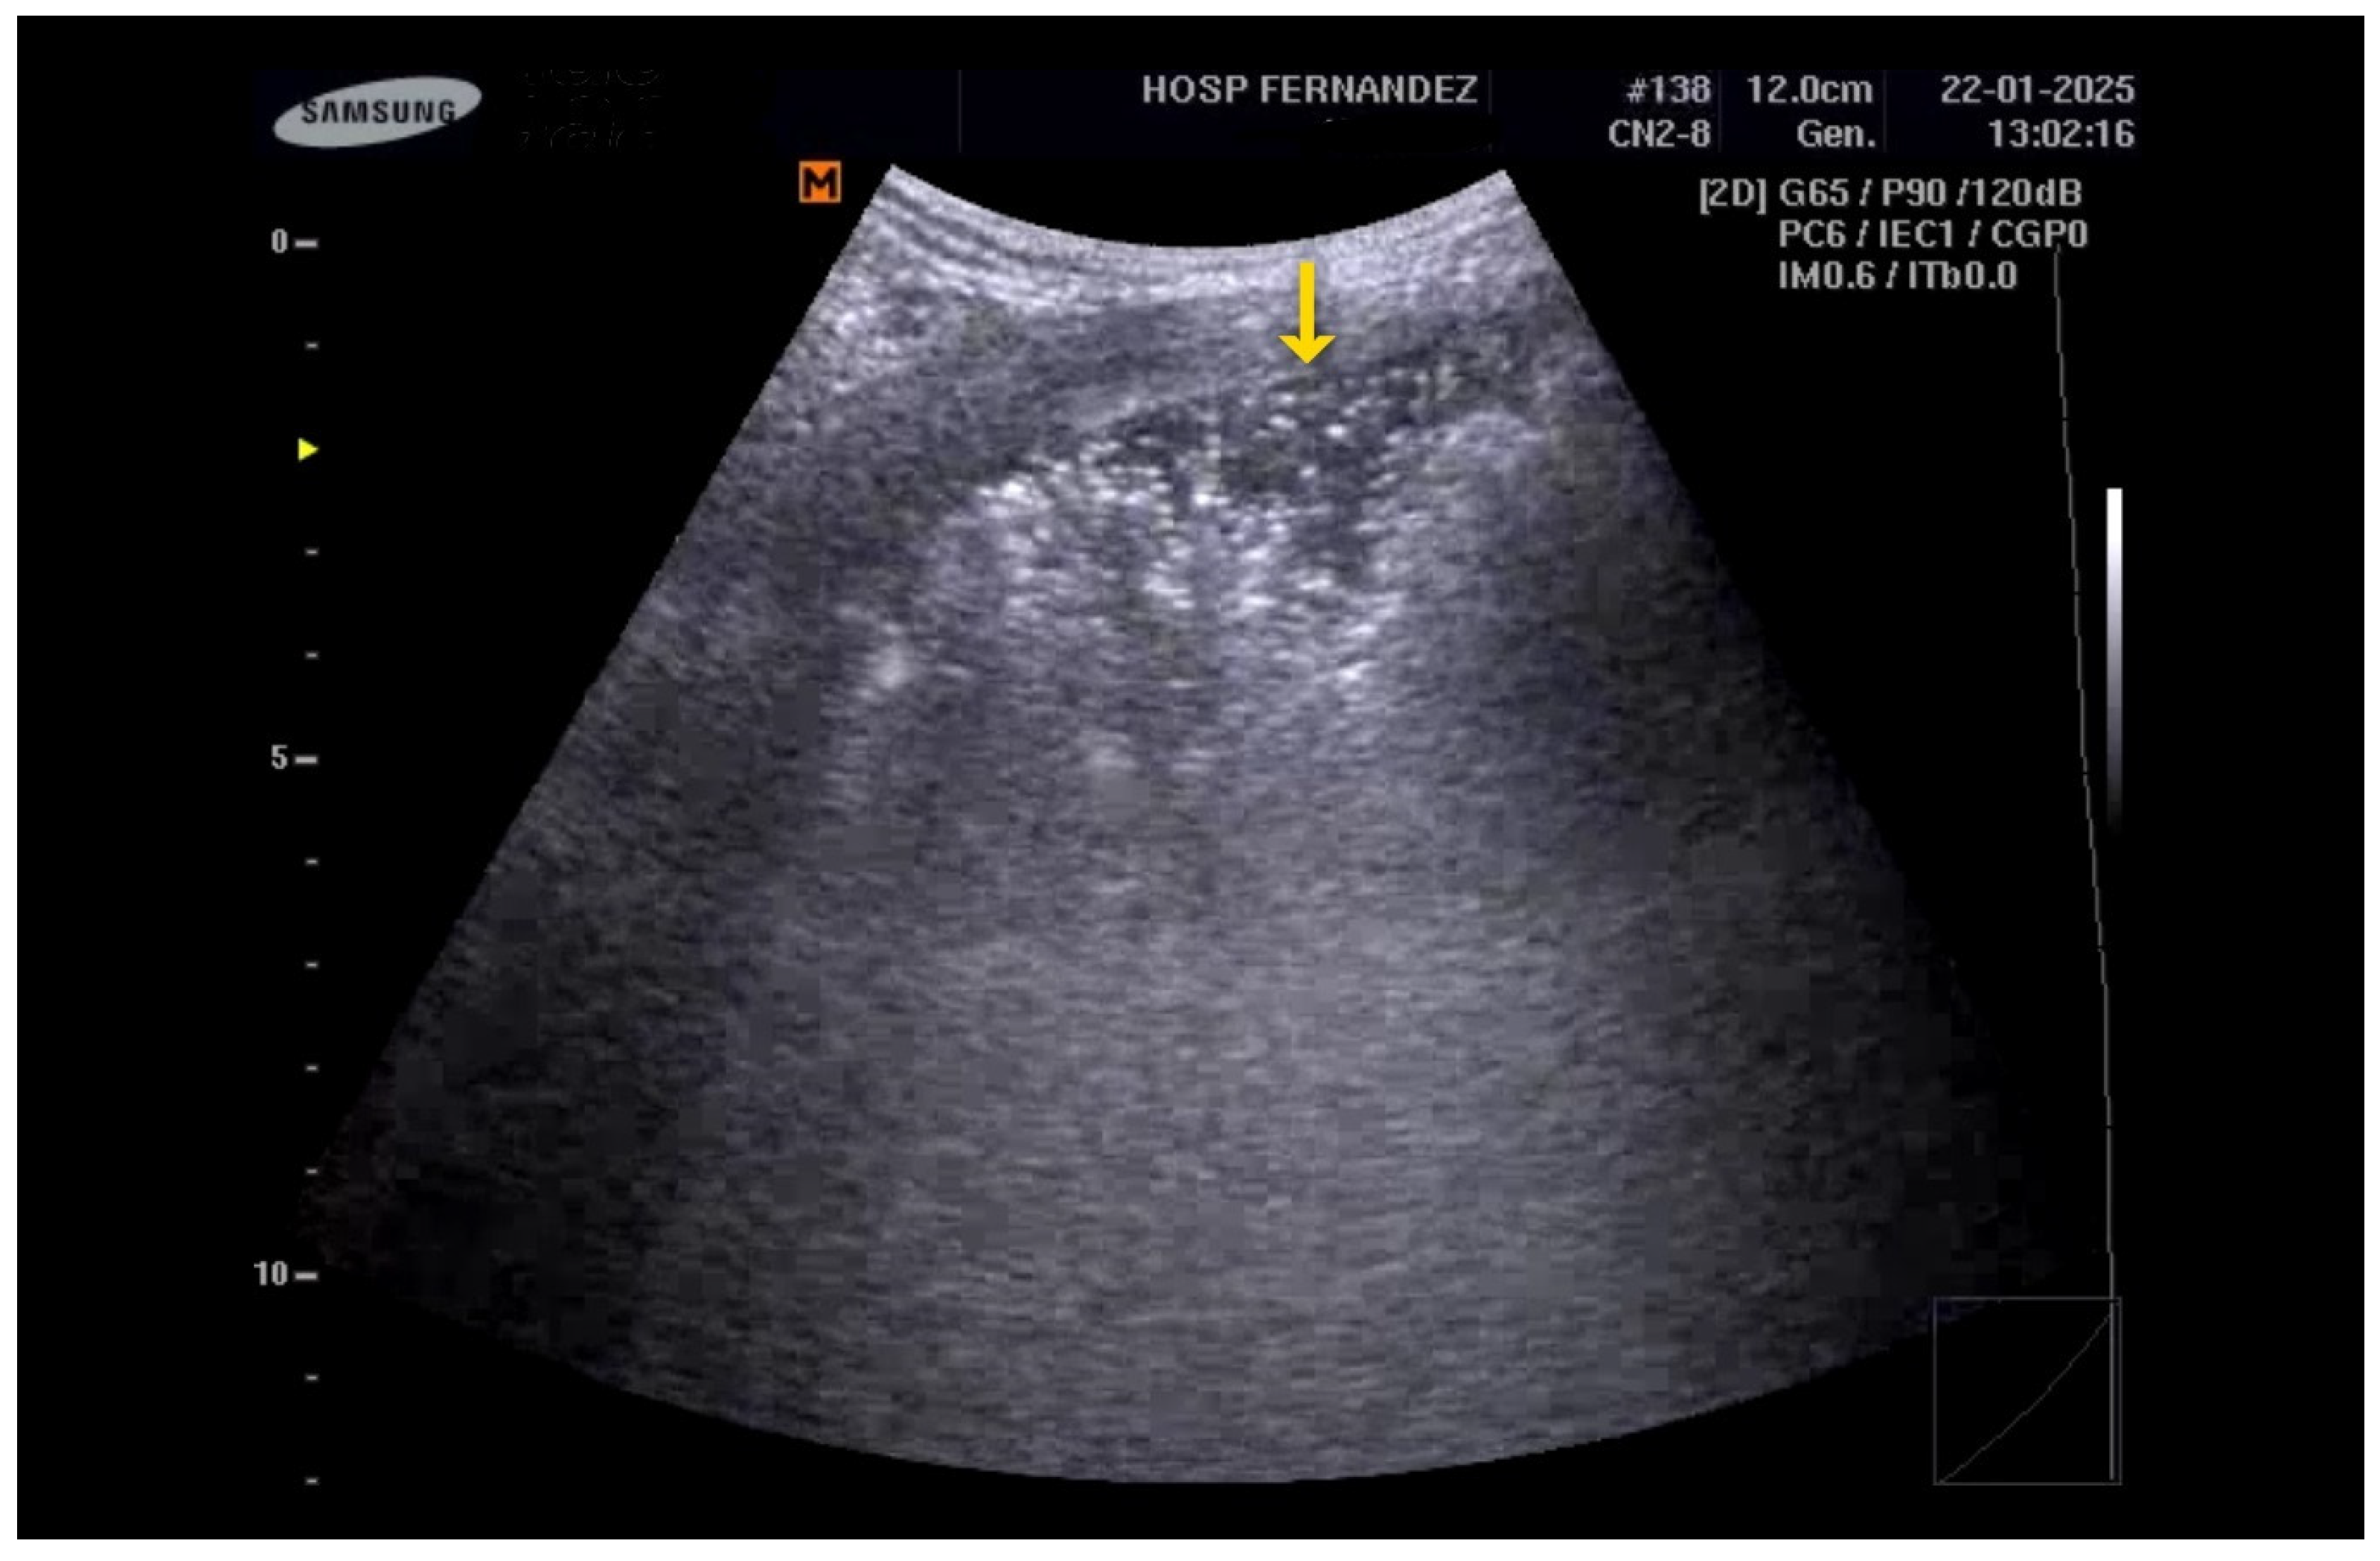

- Subpleural Abnormalities: Small echo-poor areas observed beneath the pleural line also indicate ILD. See Figure 2 and Clip S2.

Figure 2. Multiple B-lines and an irregular pleural line (yellow * and yellow ↓).

The following supporting information can be downloaded at https://www.mdpi.com/article/10.3390/healthcare13101148/s1, Clip S1: B-lines are hyperechoic artifacts descending from the pleural line to the bottom of the screen (yellow *); Clip S2: Multiple B-lines and irregular pleural line (yellow * and yellow ↓); Clip S3: Subpleural consolidation (yellow ↓) “Shred sign”; Clip S4: Consolidations with an LUS score of 3 indicate a complete loss of aeration measuring greater than 2 cm (yellow *). In addition, the preservation of the vasculature can be detected by color Doppler. Clip S5: Consolidations with an LUS score of 3 indicate a complete loss of aeration of the entire inferior right lobe (yellow *).